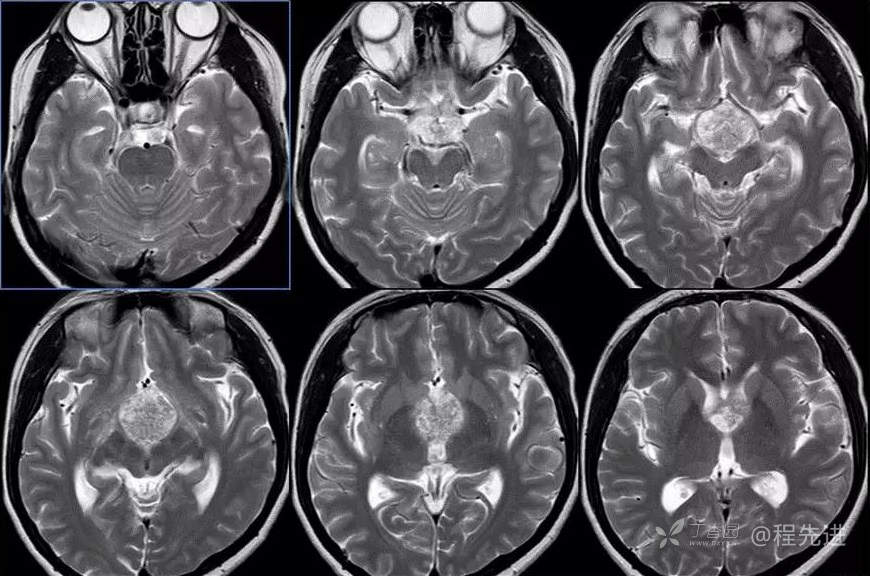

图像依次为T1横断位、T2横断位、T2FLAIR横断位、T2冠状、T1矢状、T1增强横断、矢状、冠状位